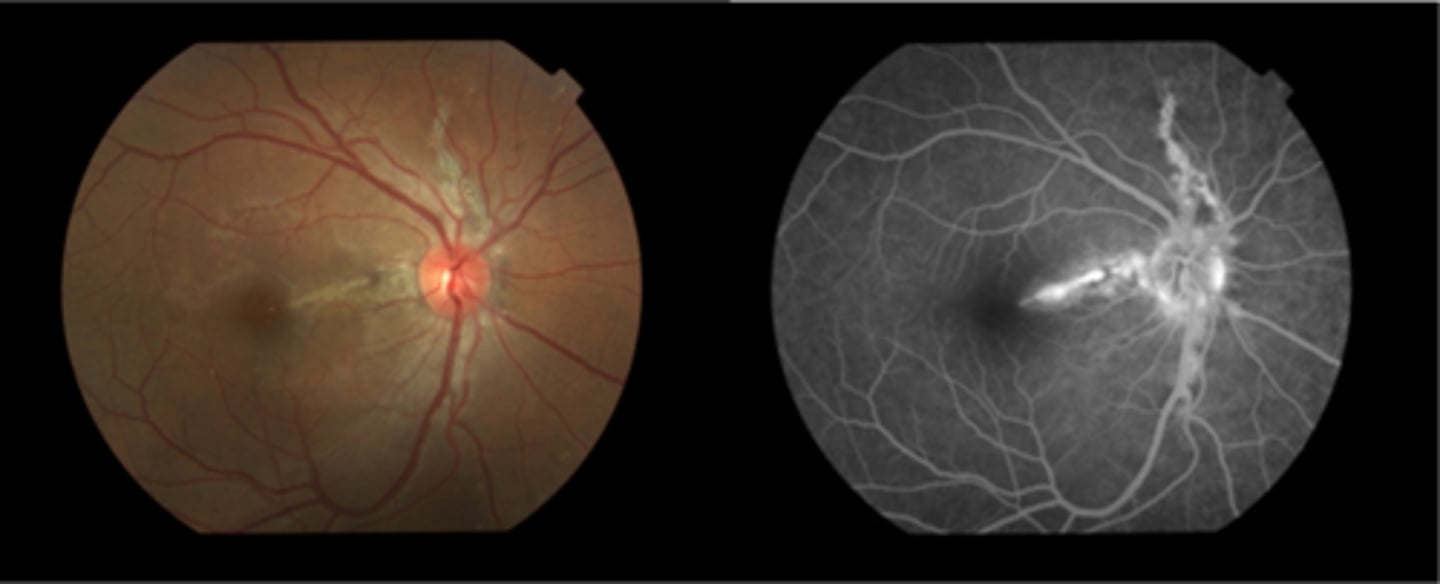

What finding of toxoplasmosis is seen in A/B?

retinitis turns into hazy scar with nerve pallor

What finding of toxoplasmosis is seen in C/D?

scarring overtime with VA loss/scotoma